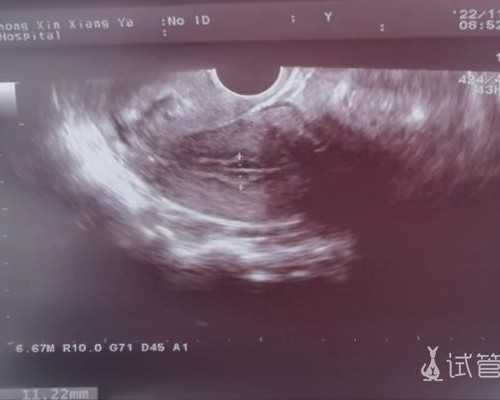

想怀孕可以吃促排卵药如果是不排卵而导致的不孕症,可以通过服用促排卵药物得到一定的治疗。促排卵药物主要用于不孕症治疗,通过促进排卵帮助无排卵或者经期不准的患者增加受孕率。排卵药物必须在专业医生的指导和跟踪监护下服用,同时在排卵期间同房可以让患者能够怀孕成功。